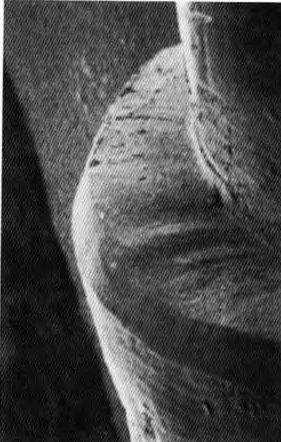

Точное препарирование осевых поверхностей зуба алмазным торпедовидным бором не имеет большого значения, поскольку препарированная поверхность все равно будет достаточно грубой. Изучение границы препарирования под увеличением обнаруживает неровности, которые невозможно воспроизвести в крае каркаса (рис. 3-16, а, Ь). Дополнительное (после алмазного бора) использование 12-гранного твердосплавного торпедовидного бора позволяет сгладить препарированную поверхность и минимизировать

Рис. 3-16а. Увеличение в 35 раз

Рис. 3-16. СЭМ осевой стенки культи зуба и границы препарирования, созданной торпедовидным j алмазным бором. Хорошо видна неровная поверхность желоба